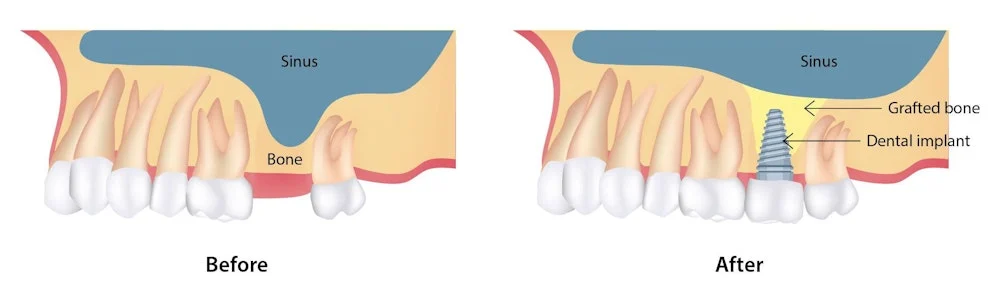

Strengthen Your Foundation for Lasting Implants

Bone grafting is a crucial procedure for patients who have insufficient bone density or volume in their jawbone to support dental implants. This process involves transplanting bone material to build up the jawbone, ensuring a stable and durable foundation for implant placement.

Restore the Natural Contour of Your Jawbone

Ridge augmentation is a procedure aimed at restoring the natural contour and volume of the jawbone. This is essential for patients who have experienced bone loss due to tooth loss, periodontal disease, or other factors. By rebuilding the ridge, we create an optimal environment for dental implant placement.